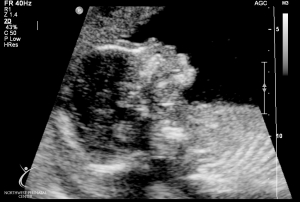

Last Ultrasound